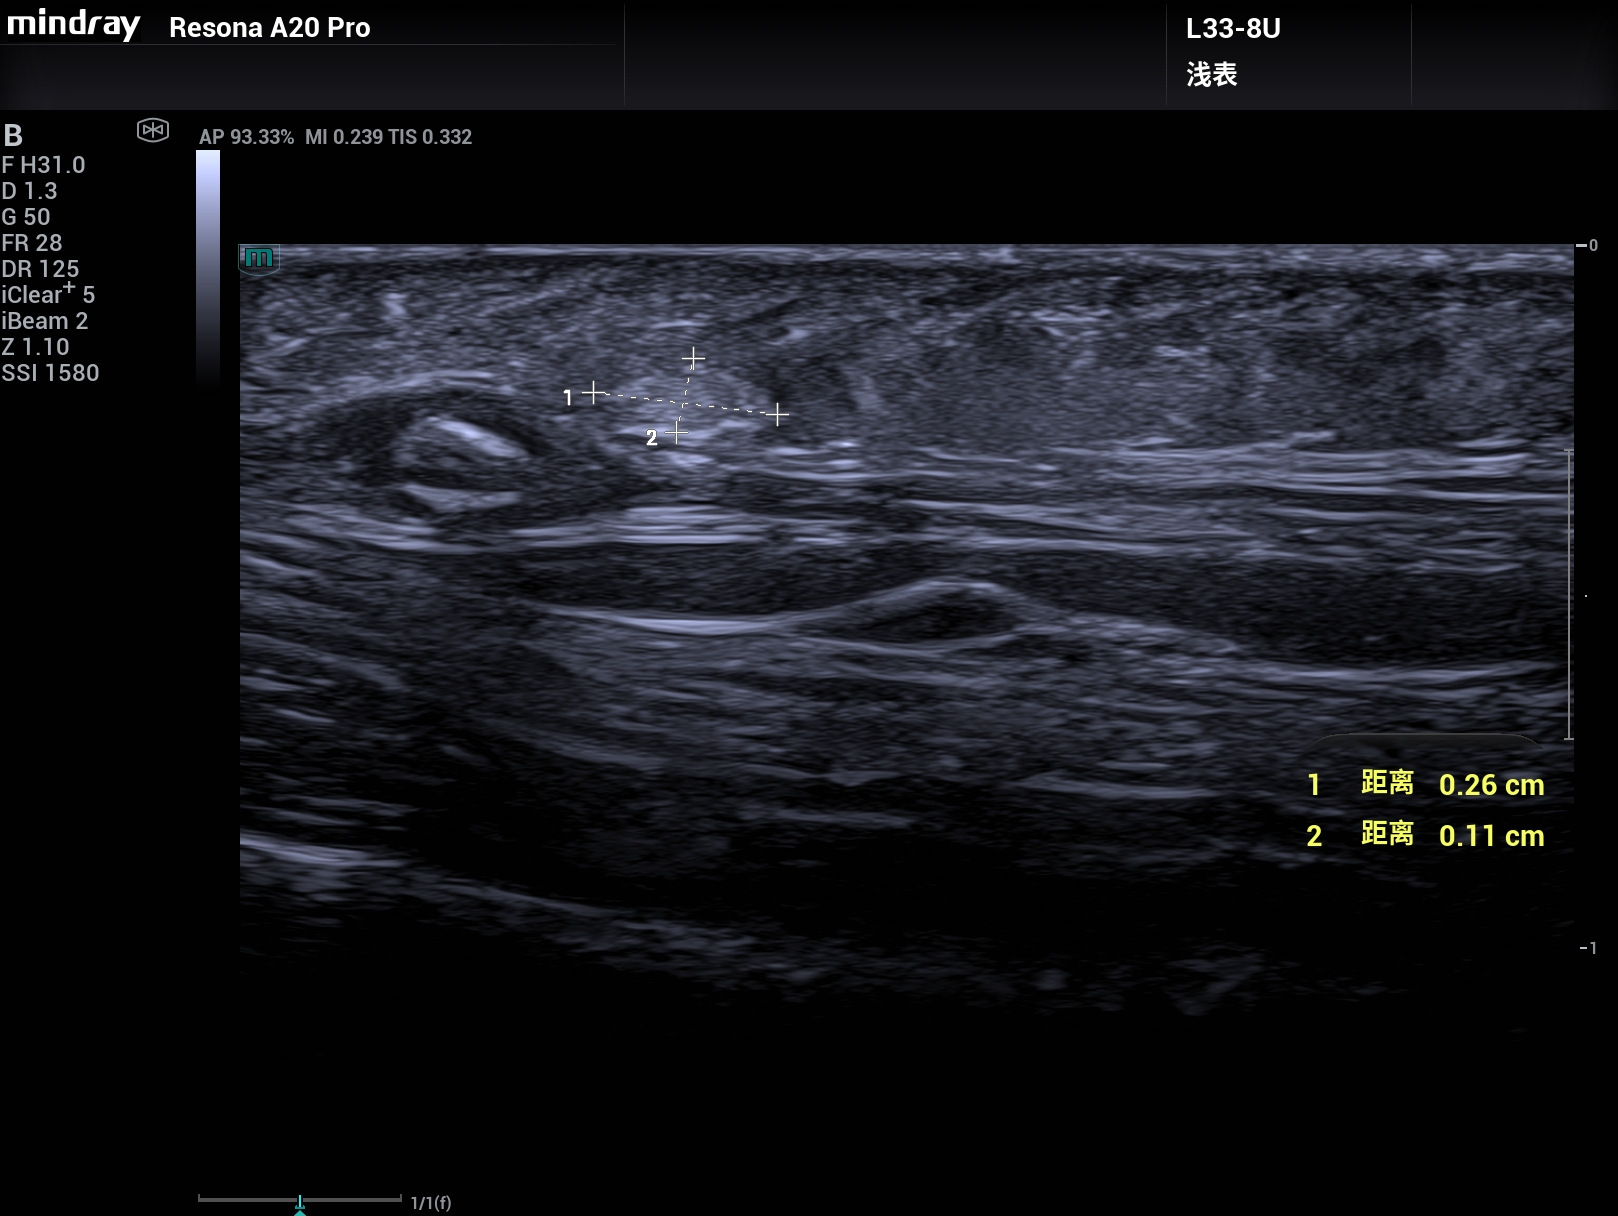

病例,33M和超微血流,头皮下1.5mm的2.6mm×1.1mm的脂肪瘤清楚显示,迈瑞Resona A20,2025年11月